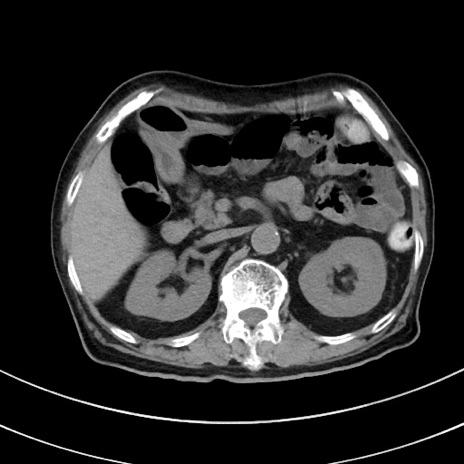

症例33(横断像)

【症例】70歳代 女性

【主訴】心窩部痛

【現病歴】延髄病変の精査・加療にて神経内科入院中。本日より心窩部痛あり。

【既往歴】虫垂炎

【身体所見】右下腹部を中心に圧痛と反跳痛あり。

【データ】WBC 10900、CRP 0.02